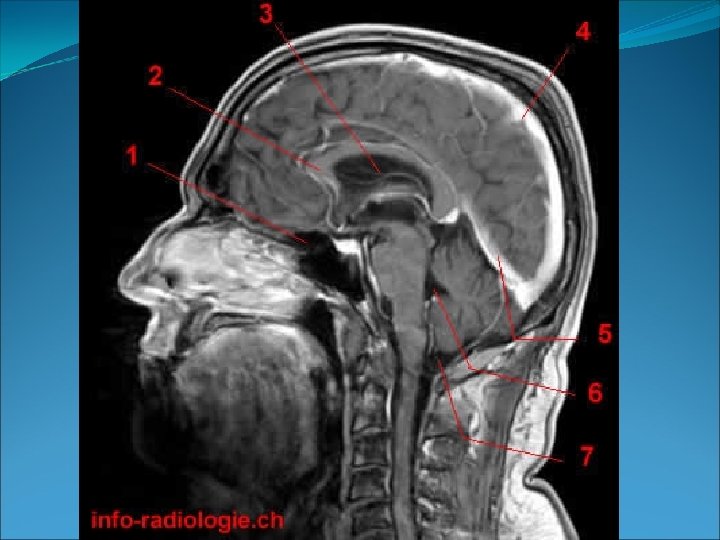

• Plano sagital (medio): es un plano vertical que divide el cuerpo en una parte derecha y otra izquierda. Se puede decir que son planos parasagitales los paralelos a la línea media (línea imaginaria que atraviesa el centro del cuerpo). 5. Eje sagital.